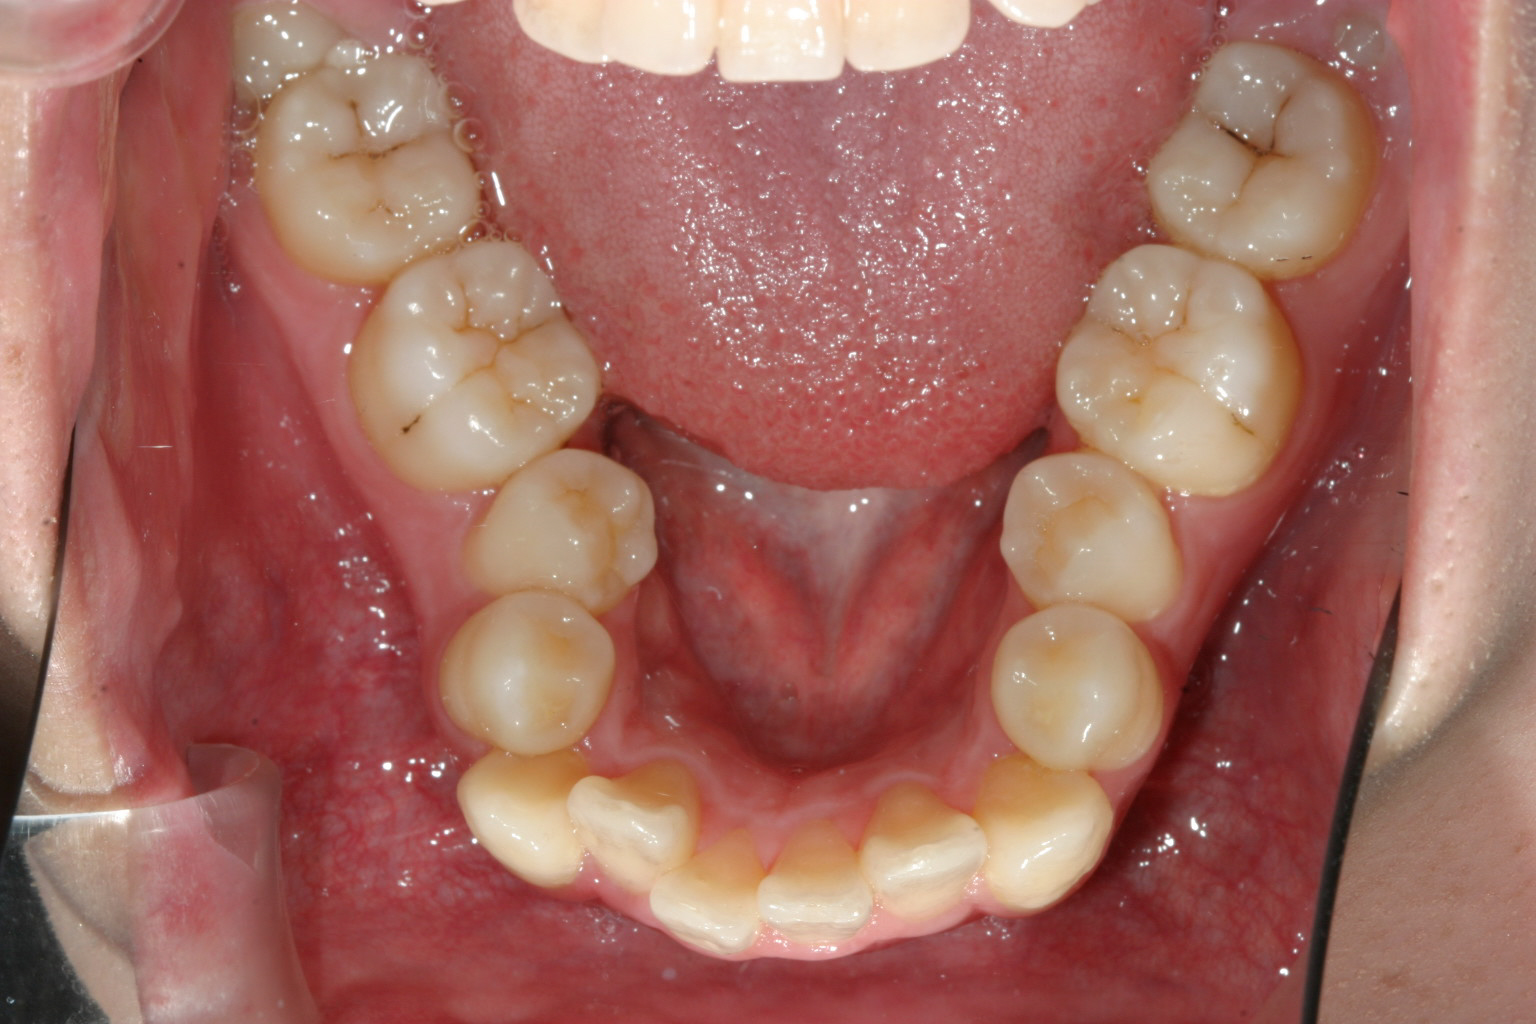

下顎はV字が特にひどく小臼歯あたりが狭くなっています。

今回の症例は稀にみる下顎のアーチフォームの乱れが激しく乱れていましたのでこれを修正するのに手間取りました。

多少下顎のアーチフォーム改善にワイヤーを使用しましたが、これだけ綺麗になれば患者様にも満足して頂けました。